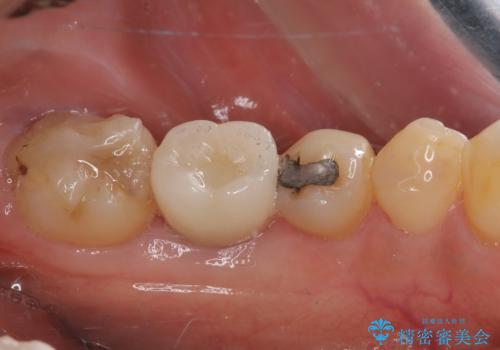

下顎大臼歯の抜歯即時埋入インプラント治療では、複数ある歯根のうち、後方の歯根部にインプラントを埋入することで一般的であり、今回破折して骨吸収が著しいのは前方の歯根であったため、事前に仮歯を用意した上で、抜歯即時埋入インプラントによる補綴治療を行うこととしました。

来院されるまではインプラント治療を躊躇されていましたが、抜歯即時埋入により、単回の外科処置で治療が終えられることのメリットを理解され、インプラントによる補綴治療を行いました。

スムーズに治療を終えることができました。